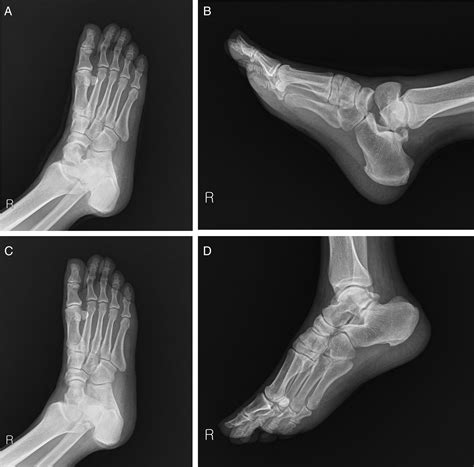

Talus Fracture | Dr Bijan 4 Feet